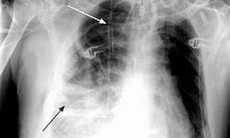

Hình ảnh Xquang phổi của bệnh nhân mắc viêm mủ màng phổi

Kết quả xét nghiệm cho thấy số lượng bạch cầu tăng, CRP tăng, PCT tăng, Lactat tăng. Xquang mờ góc sườn hoành thường một bên, có thể mờ hoàn toàn một bên phổi, trung thất bị đẩy bên phía đối diện…